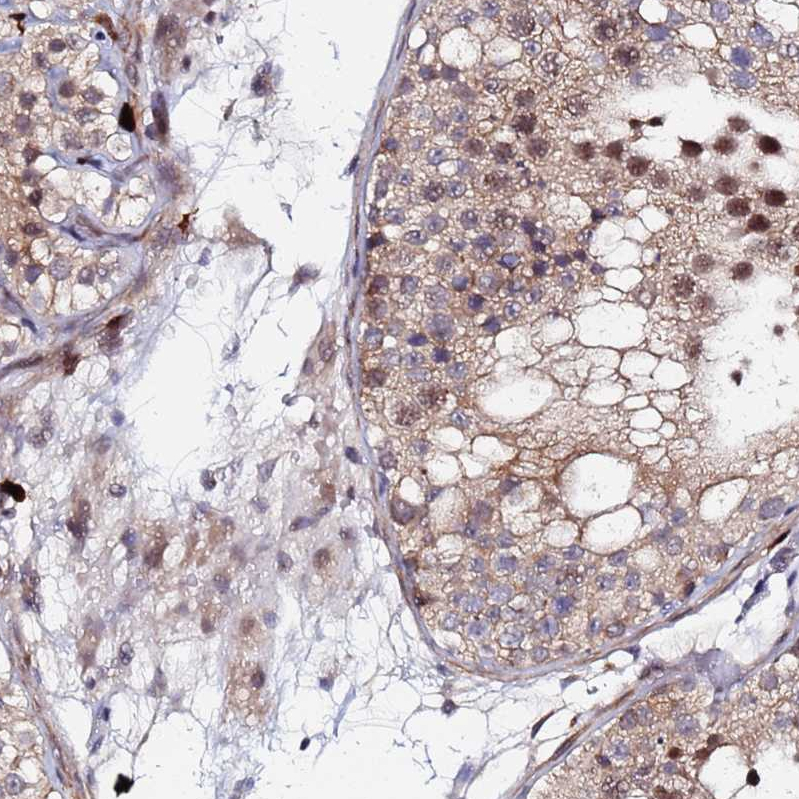

Immunohistochemical staining of human urinary bladder shows moderate cytoplasmic/nuclear positivity in urothelial cells with additional membranous positivity.